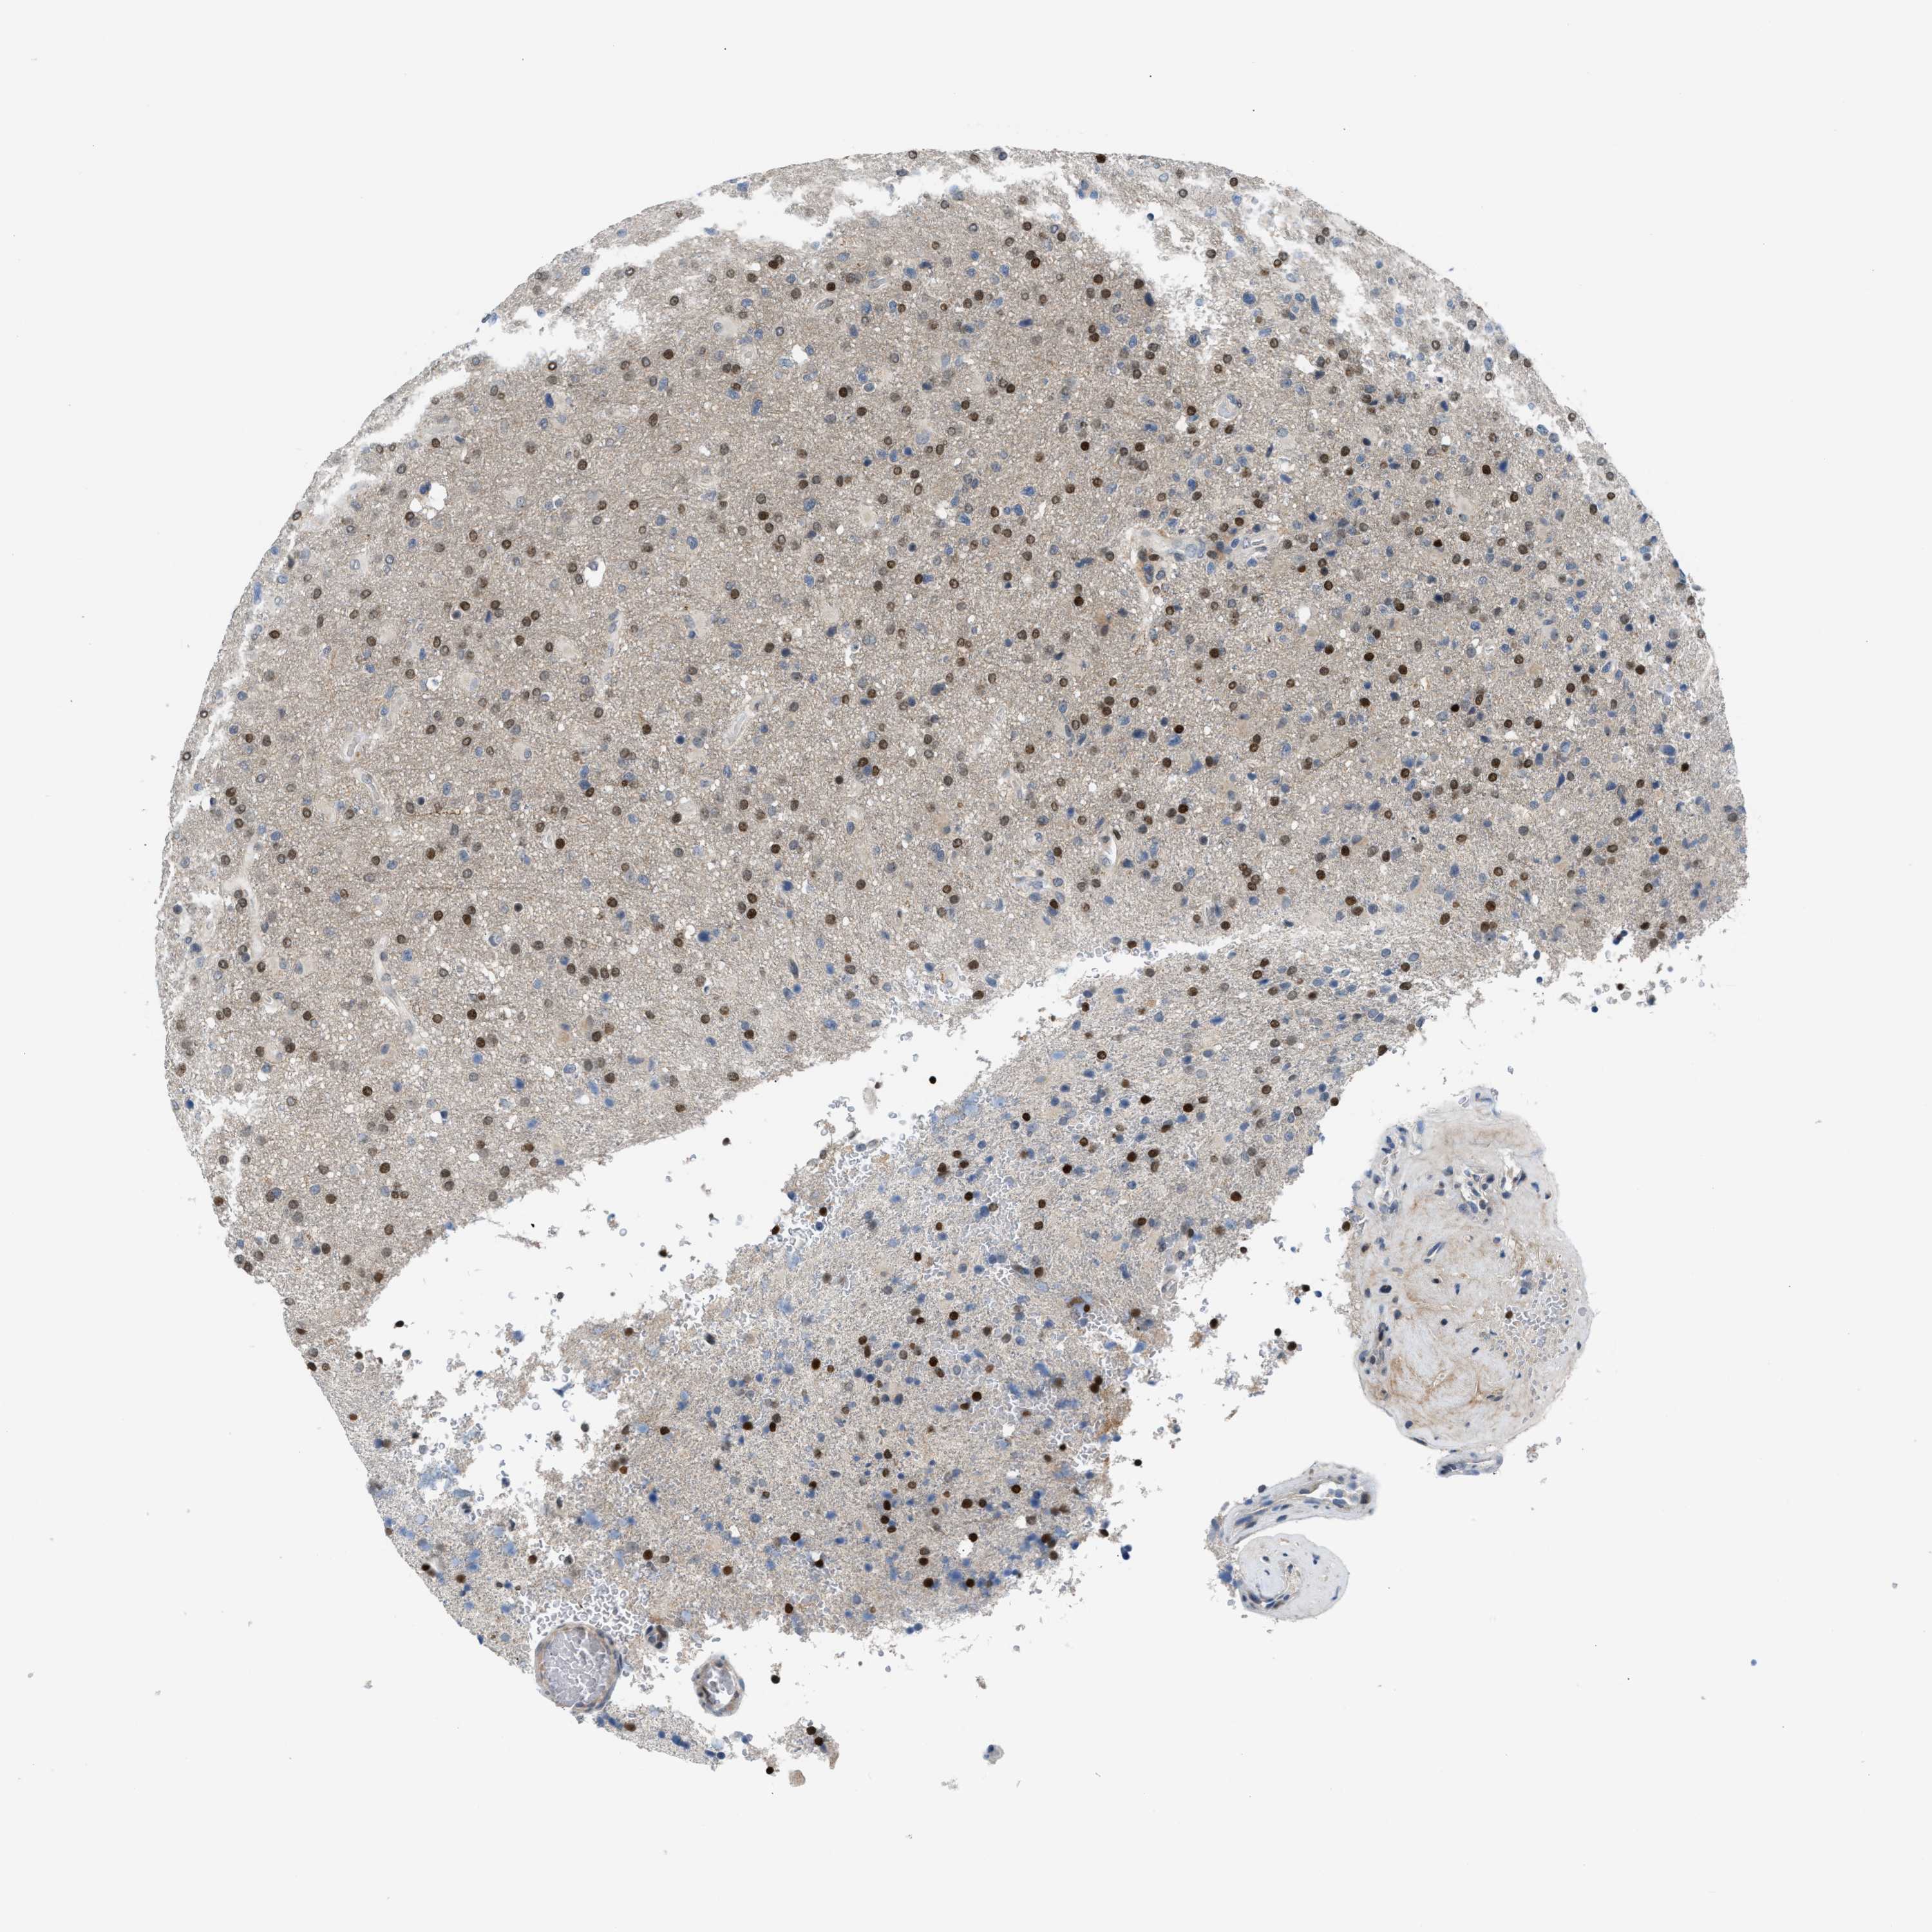

GLIOMA - Protein expressioni

A mouse-over function shows sample information and annotation data. Click on an image to view it in a full screen mode. Samples can be filtered based on level of antibody staining by selecting one or several of the following categories: high, medium, low and not detected. The assay and annotation is described here.

Note that samples used for immunohistochemistry by the Human Protein Atlas do not correspond to samples in the TCGA dataset.

Antibody stainingi

Antibody staining in the annotated cell types in the current human tissue is reported as not detected, low, medium, or high, based on conventional immunohistochemistry profiling in selected tissues. This score is based on the combination of the staining intensity and fraction of stained cells.

Each image is clickable and will lead to virtual microscopy that enables deeper exploration of all samples and also displays staining intensity scores, fraction scores and subcellular localization as well as patient and tissue information for each sample.

Antibody CAB020139

Staining

High

Medium

Low

Not detected

Intensity

Strong

Moderate

Weak

Negative

Quantity

>75%

75%-25%

<25%

None

Location

Nuclear

Cytoplasmic/membranous

Cytoplasmic/membranous,nuclear

Glioma, malignant, High grade

Glioma, malignant, Low grade